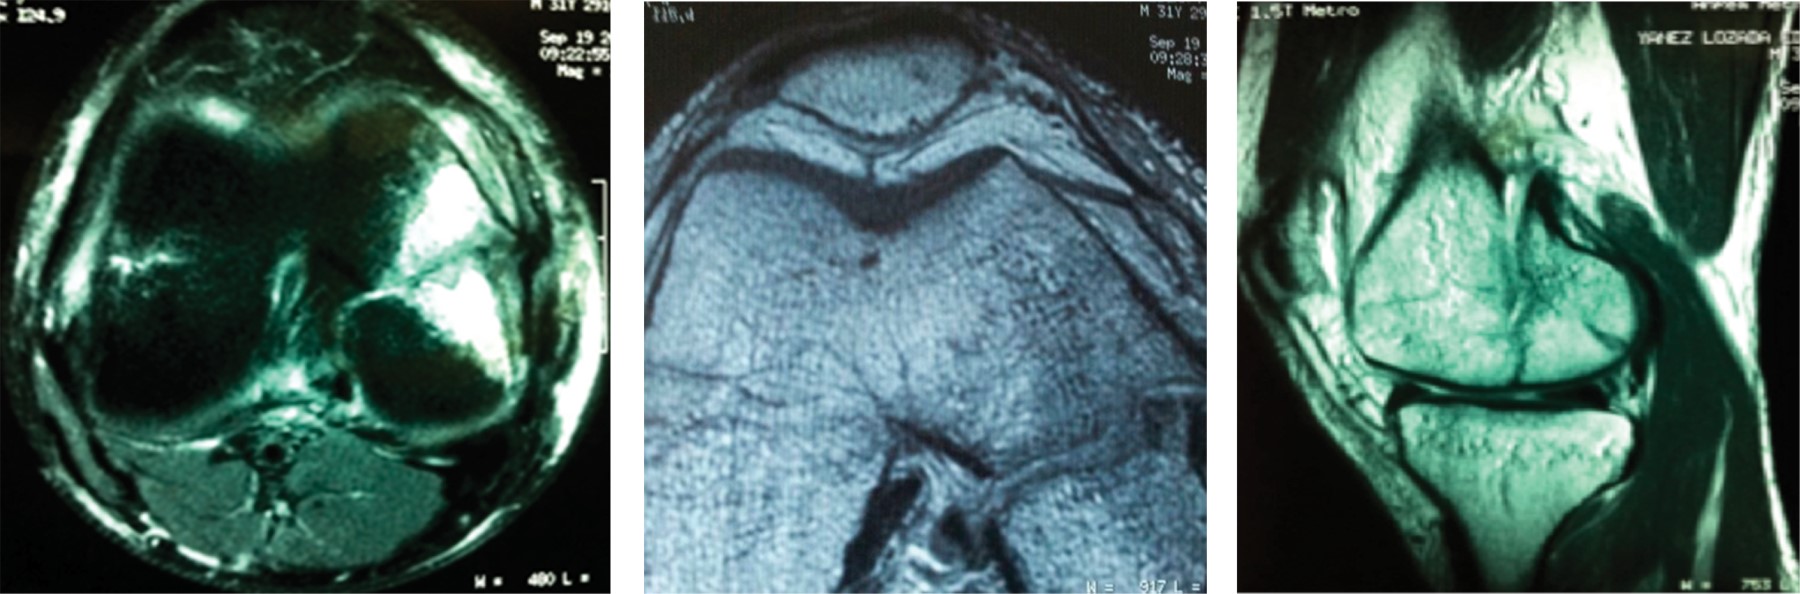

Introduction: knee femoral condyle coronal fractures or Hoffa fractures are among the rarest fractures of the pelvic limb, being even more rare those of the medial condyle. The success in the management of these patients lies in the timely diagnosis and the consequent anatomical reduction of the femoral articular surface. Clinical case: the objective of this article is to present a patient with right medial Hoffa fracture, registered as a single case in the archives of our hospital. The patient was referred to us on November 2011, with a 10-day course after suffering a fall from horse ridding, presenting a forced varus mechanism and direct contusion of the right knee. He shows an anteroposterior and lateral knee X-rays showing a subtle solution of continuity in the coronal plane of the base of the medial condyle, corroborated with magnetic resonance imaging and was also associated with a non-surgical partial injury of both menisci and the anterior cruciate ligament. Surgical intervention was performed on 27th/11/2011, through open reduction with a medial approach and internal fixation with 7.0 mm (x2) cannulated screws. The patient was discharged with early and continuous mobilization of the knee, deferring support and rehabilitation until the 6th week. He is currently a wandering patient, asymptomatic, with complete range of motion. Because respecting the extensor apparatus through a medial approach and the articular surface with cannulated screws, it was observed in consequence an adequate evolution of our patient, being able to return to his daily activities, even remount.

Figure 1